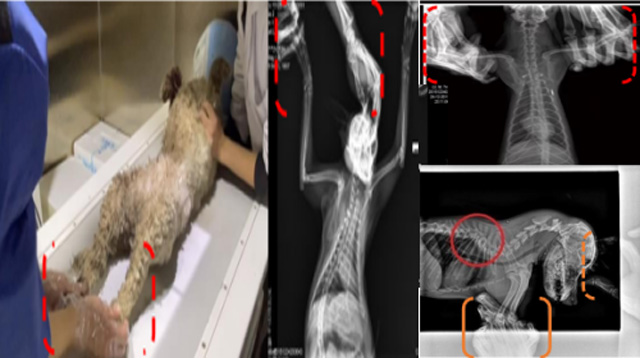

現(xiàn)在寵物醫(yī)療設(shè)備得到高速發(fā)展,現(xiàn)在有越來越多的寵物診療機(jī)構(gòu)配置X射線裝置如寵物DR。寵物骨折或者有其他疾病不能通過直觀看出來的。寵物診所醫(yī)生都會(huì)使用寵物DR來做輔助檢查。但是有時(shí)候?qū)櫸镝t(yī)生沒有加強(qiáng)防護(hù),就在寵物DR室給寵物拍X片做檢查。這樣也是會(huì)受到X射線的輻射。因?yàn)閄射線上崗是屬于職業(yè)病危害崗位。長期的輻射會(huì)對(duì)人體造成一定的危害。寵物醫(yī)生也需要接受X射線照射的上崗前都必須進(jìn)行放射工作人員的職業(yè)健康體檢。體檢不合格的話是不能擔(dān)任放射工作的。未經(jīng)上崗前職業(yè)健康體檢的勞動(dòng)者從事接觸職業(yè)病危害作業(yè)的行為,已經(jīng)違反了《中華人民共和國職業(yè)病防治法》第三十五條規(guī)定,依據(jù)《中華人民共和國職業(yè)病防治法》第七十五條規(guī)定,需要進(jìn)行整改罰款。開展寵物放射診療活動(dòng),在日常工作中,對(duì)本機(jī)構(gòu)的X射線危害的職業(yè)病防治,需要知道并做到以下內(nèi)容: